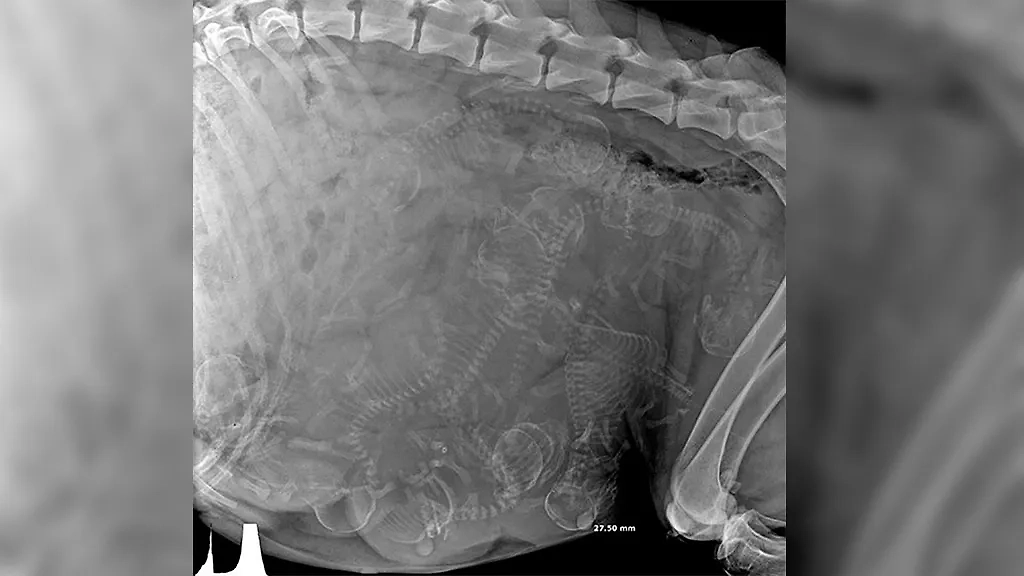

"Беременная собака", — RyanReynoldsWrap.

Фото © Reddit / RyanReynoldsWrap